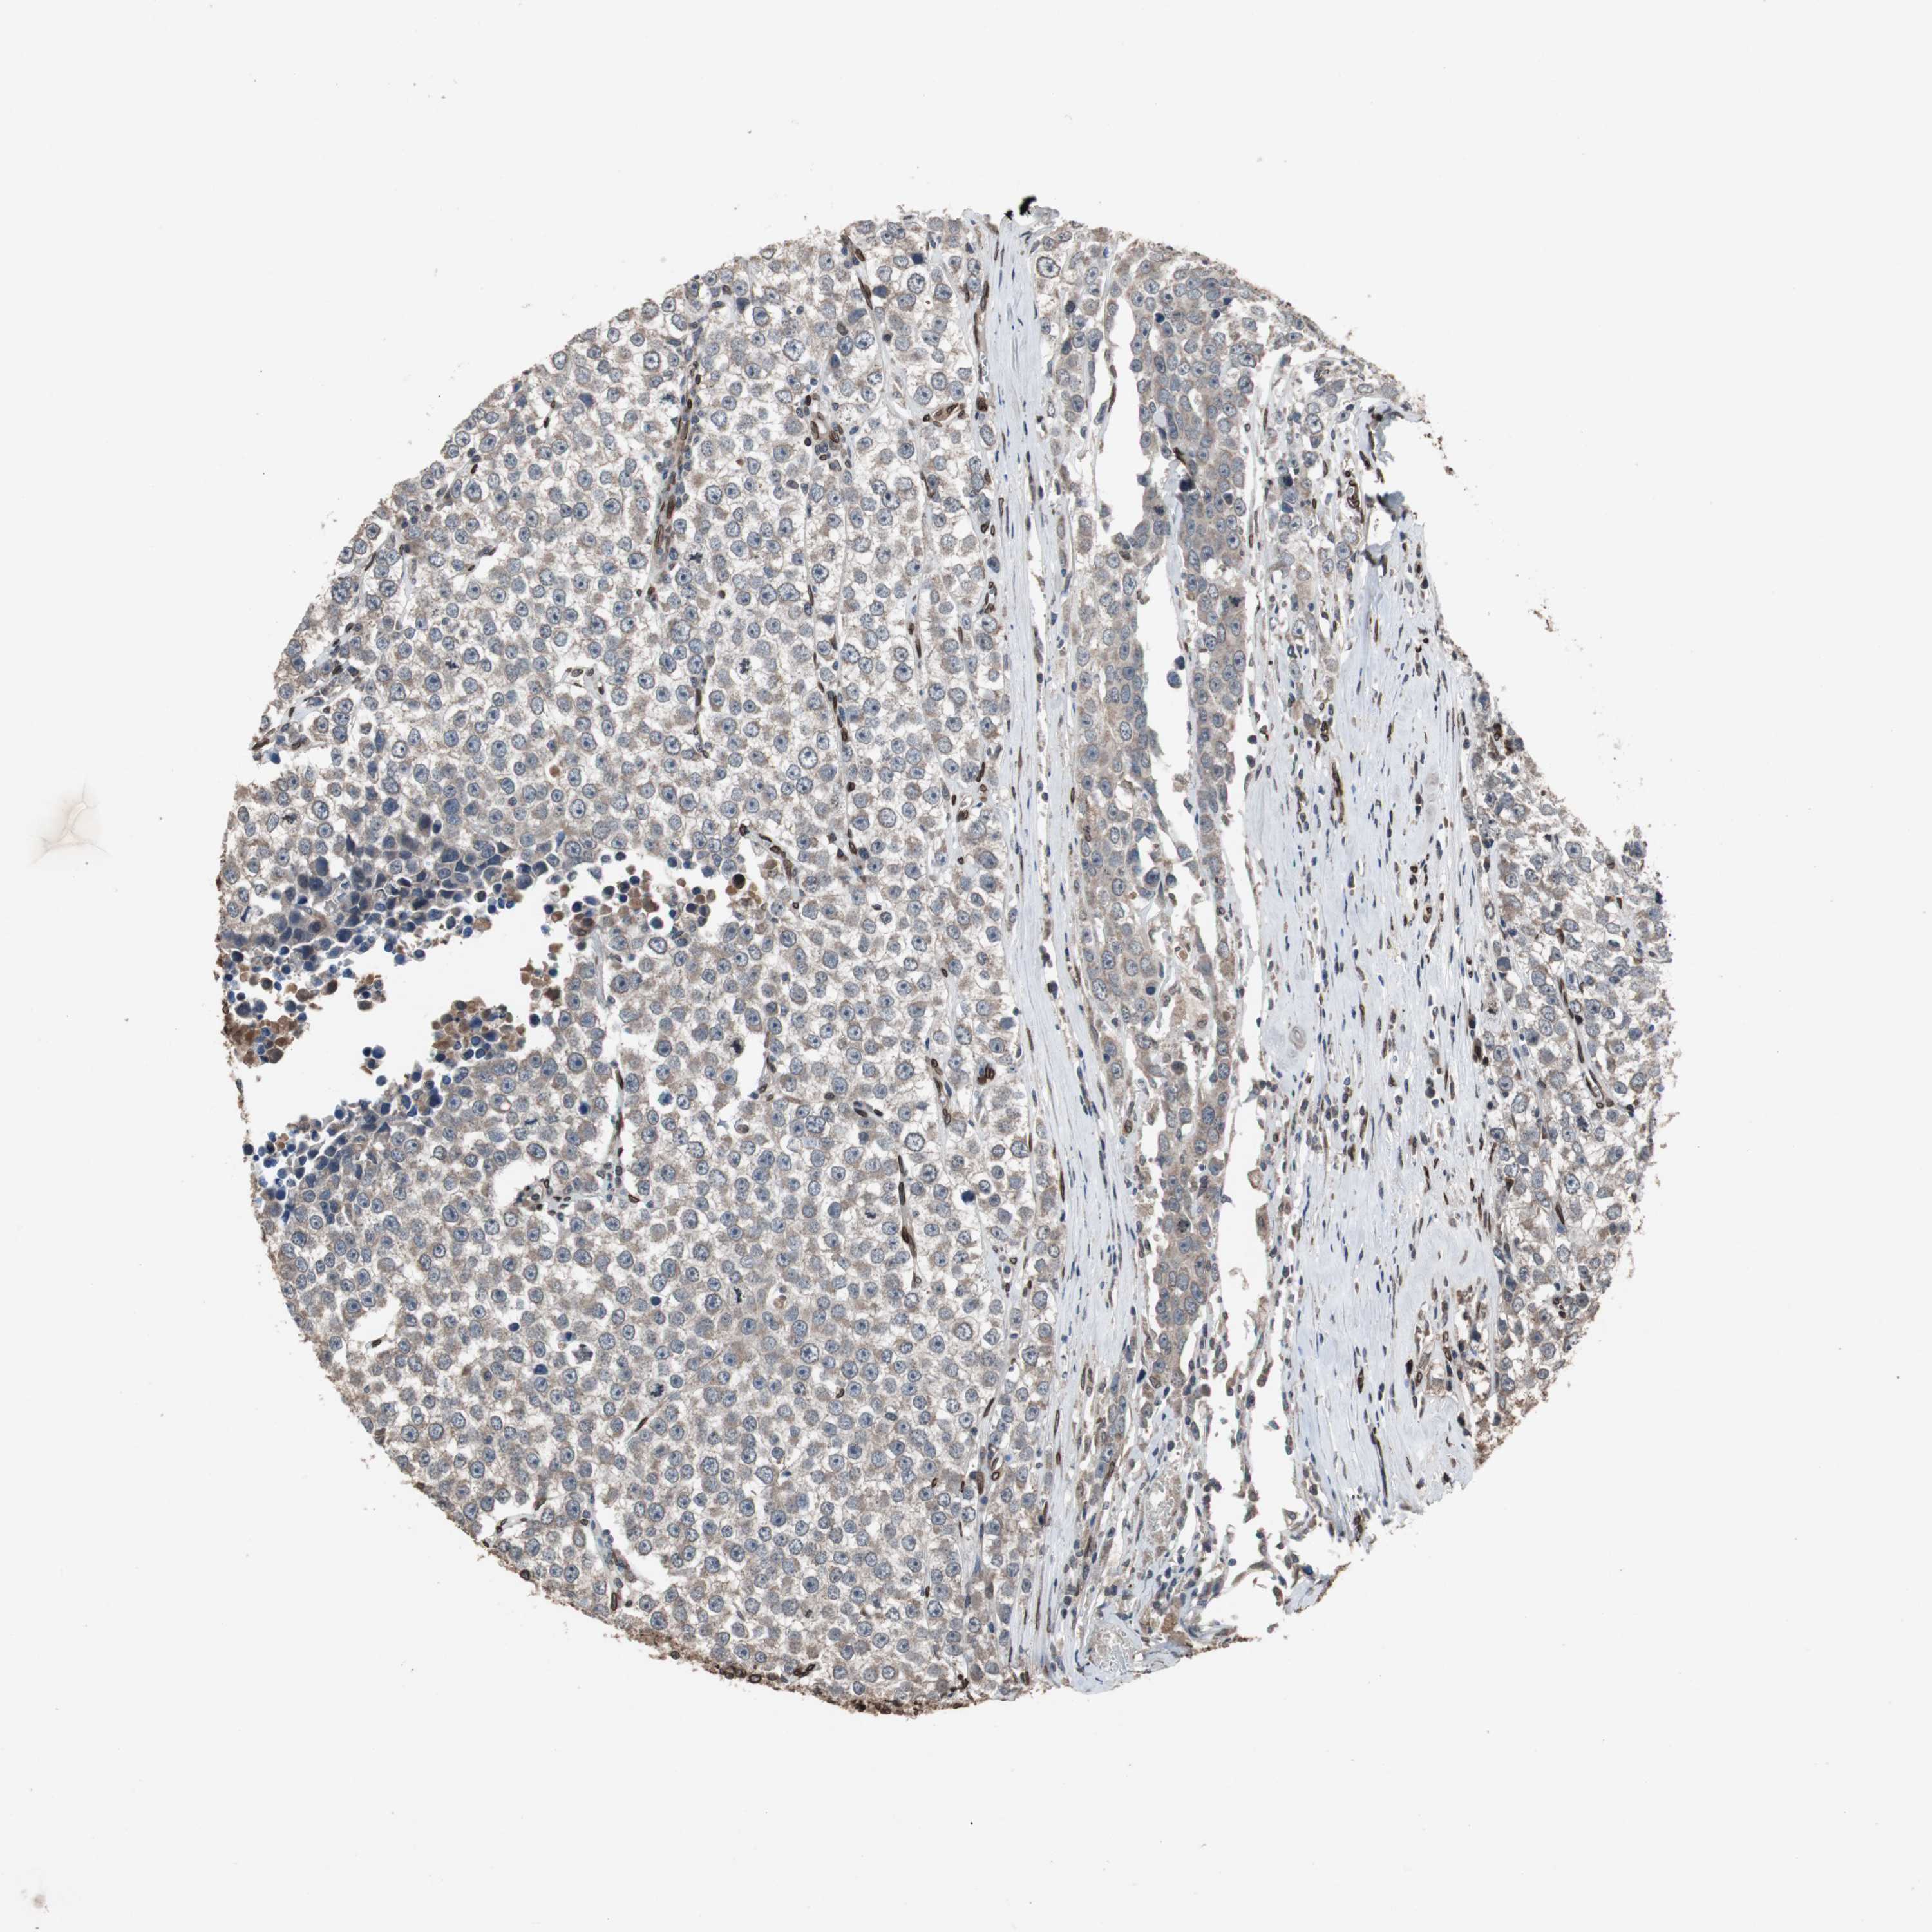

TESTIS CANCER - Protein expressioni

A mouse-over function shows sample information and annotation data. Click on an image to view it in a full screen mode. Samples can be filtered based on level of antibody staining by selecting one or several of the following categories: high, medium, low and not detected. The assay and annotation is described here.

Note that samples used for immunohistochemistry by the Human Protein Atlas do not correspond to samples in the TCGA dataset.

Antibody stainingi

Antibody staining in the annotated cell types in the current human tissue is reported as not detected, low, medium, or high, based on conventional immunohistochemistry profiling in selected tissues. This score is based on the combination of the staining intensity and fraction of stained cells.

Each image is clickable and will lead to virtual microscopy that enables deeper exploration of all samples and also displays staining intensity scores, fraction scores and subcellular localization as well as patient and tissue information for each sample.

Antibody HPA006660

Antibody CAB004022

Staining

High

Medium

Low

Not detected

Intensity

Strong

Moderate

Weak

Negative

Quantity

>75%

75%-25%

<25%

None

Location

Nuclear

Cytoplasmic/membranous

Cytoplasmic/membranous,nuclear

Carcinoma, Embryonal, NOS

Seminoma, NOS